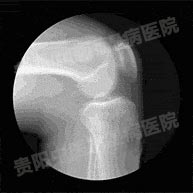

如何才能检查出是否患上风湿性关节炎?2016-12-04

做好检查 步,治好风湿性关节炎2015-05-12